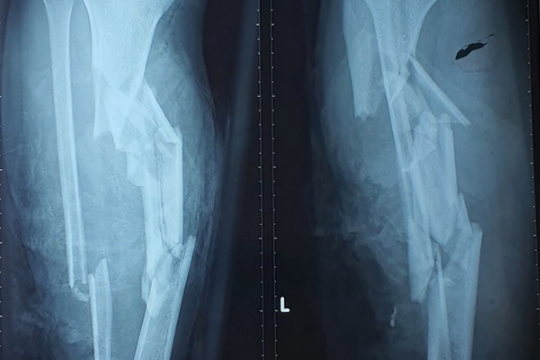

Hãi hùng với hình ảnh hai chân gãy nát vì bị chân vịt ca nô chém

Khi anh Chí Th. đang làm việc trên sông thì bất ngờ bị chiếc ca nô chạy lùi tông trúng rồi cuốn cơ thể vào vùng chân vịt. Vụ việc khiến nạn nhân bị thương tích nặng, 2 chân gãy nát.